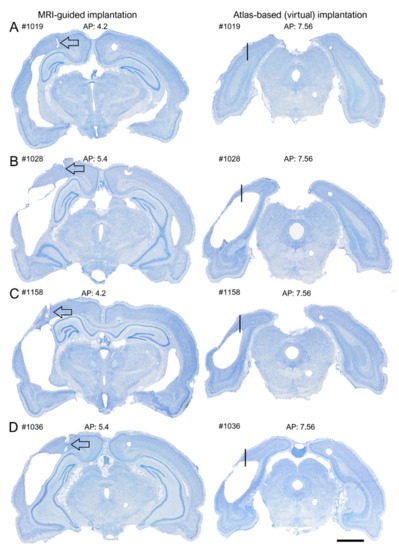

Finally, to assess whether the MRI images indeed improved the targeting of the electrode tip to the perilesional cortex, and not, for example, to the lesion cavity, we reexamined the histological sections of TBI rats in the MRI cohort. We focused on the caudal aspect of the brain, as targeting this area without the use of MRI was challenging due to remarkable TBI-related cortical atrophy.

A hypothetical “virtual” electrode was placed at the atlas-defined coordinate of the posterior intracortical electrode (Figure 10). We then reconstructed the destination of the electrode tip in the available histological sections by assessing (a) whether it was located in the cortex or lesion cavity and (b) the distance of the tip from the lesion edge. We found that by using the atlas-based coordinate (AP −7.56), 58% (18/31) of the electrodes had been in the lesion cavity compared with 0% for the MRI-guided implantations (Figure 5C and Figure 10 and Table 2). The remaining 42% (13/31) of the “virtual” electrodes were located medial to the lesion cavity, except in one case (rat 1103), in which the tip location was caudal to the lesion. The average distance of the electrode tip to the lesion edge was 0.64 ± 0.1 mm (range: 0–1.3 mm) (see also Supplementary Table S2 for further details).